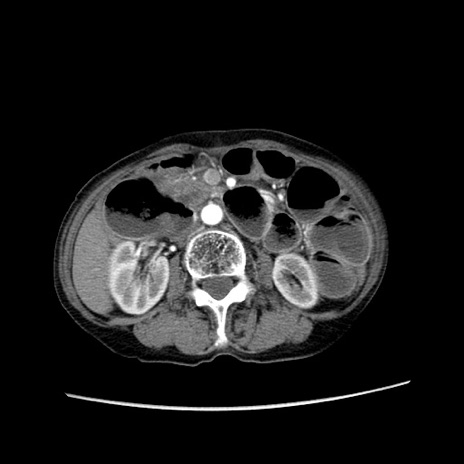

症例25(横断像)

【症例】80歳代女性

【主訴】胸のつかえ感

【現病歴】約9時間前に食後から胸のつかえた感じあり、嘔吐あり、来院。

【既往歴】胃癌(全摘)、胆摘、虫垂炎

【身体所見】心窩部に圧痛あり、反跳痛なし。

【データ】WBC 5700、CRP 0.05